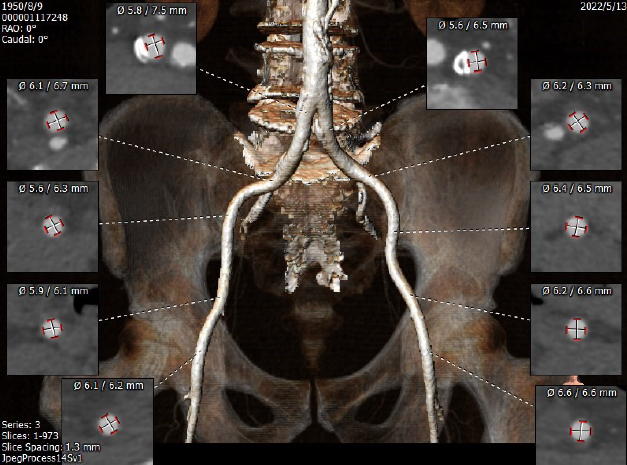

入路两侧血管分叉高度可,无迂曲。左侧血管平均最小内径6.1mm,右侧血管平均最小内径6.0mm。